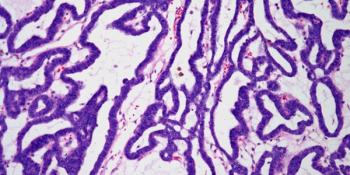

A biopsy is taken from the prostate of a 59-year-old man. Based on the image shown, what is your diagnosis?